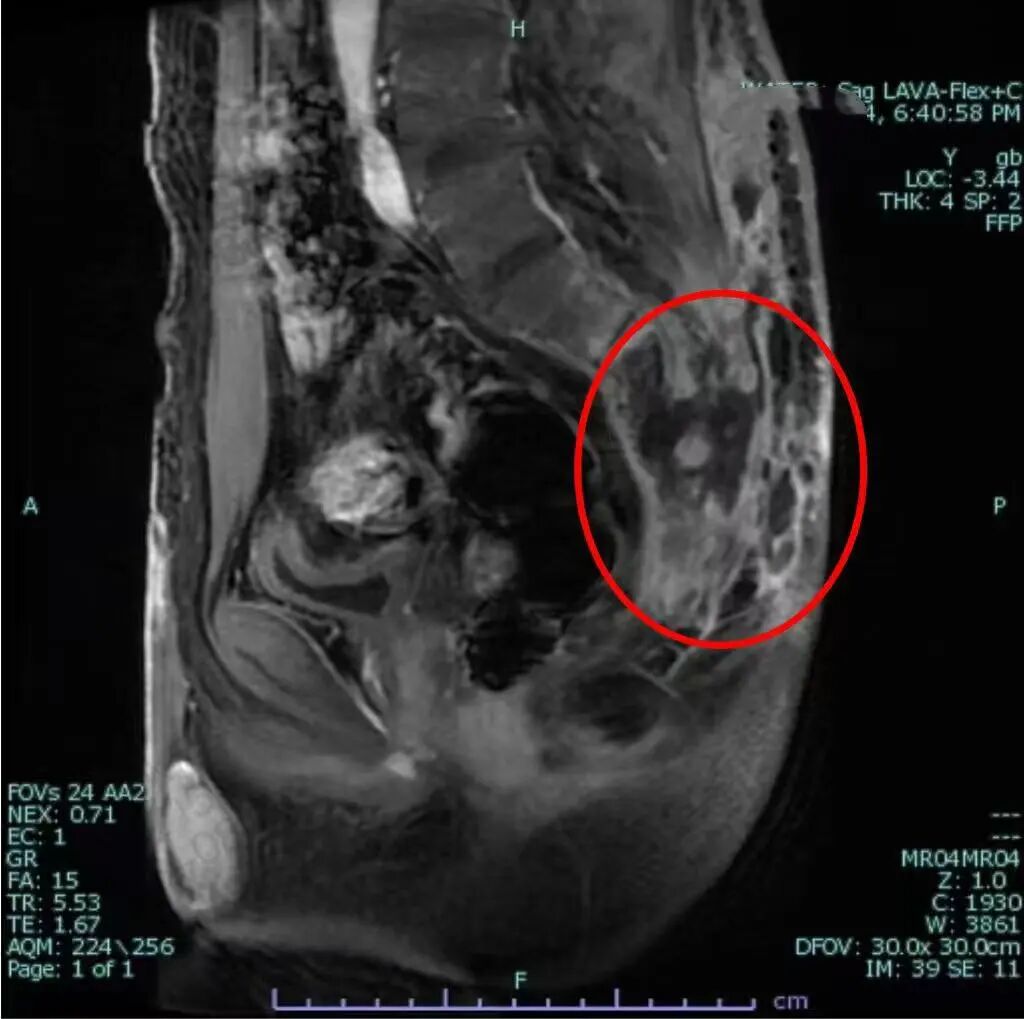

圖片

放療結(jié)束2個(gè)月后復(fù)查盆腔核磁示:骶尾骨及周圍臀部軟組織異常信號(hào)較前范圍縮小

最終,患者慕名來到滄州市中心醫(yī)院婦科、血液與皮膚軟組織腫瘤放療科(放療三科)。面對(duì)這一復(fù)雜棘手的病例,高雅麗主任帶領(lǐng)科室團(tuán)隊(duì)為其量身定制了一套詳盡的個(gè)體化“放療+化療+免疫治療”方案。治療過程中,醫(yī)生們憑借精湛的技術(shù)精準(zhǔn)施治,在最大限度地殺滅癌細(xì)胞的同時(shí),全力保護(hù)周圍正常組織;護(hù)理團(tuán)隊(duì)則給予了患者無微不至的關(guān)懷和專業(yè)的疼痛、傷口護(hù)理,幫助其對(duì)抗感染、緩解痛苦、增強(qiáng)信心。